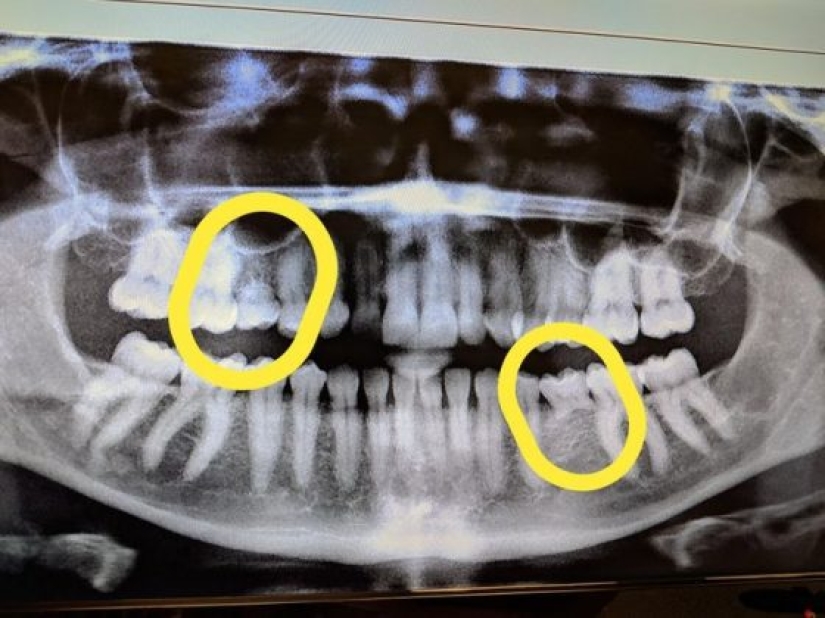

11. “En este momento, el hada de los dientes me debe mucho dinero. Tengo 33 años y aquí están mis radiografías que muestran los dientes de leche que me quedan”.